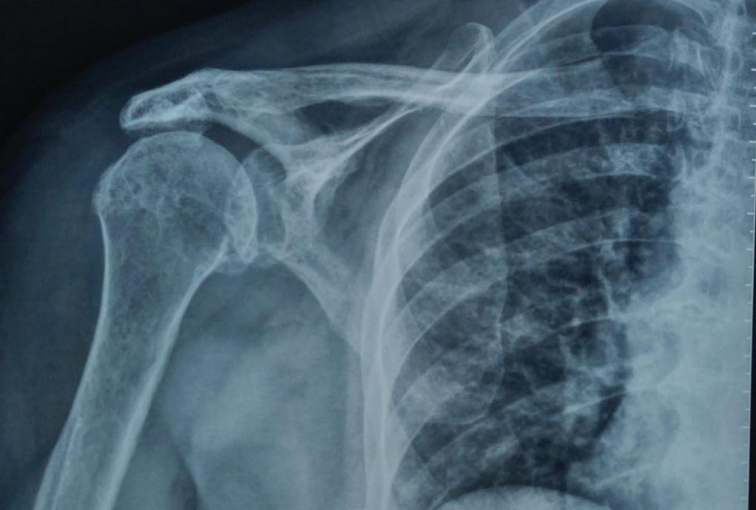

Seeking the blessings of His Holiness Jagadguru Dr. Sri Shivaratri Rajendra Mahaswami ji and offering our humble pranams to His Holiness Jagadguru Sri Shivarathri Deshikendra Mahaswami ji, JSS Hospital has achieved a historic milestone in healthcare. For the very first time in Mysuru, the Department of Orthopedics successfully performed a Reverse Total Shoulder Arthroplasty (RTSA) using state of the art Virtual Implant Positioning (VIP) technology by Arthrex.

Reverse Total Shoulder Arthroplasty is a sophisticated surgical solution designed for patients with severe shoulder dysfunction, particularly when conventional shoulder replacement proves ineffective. Individuals suffering from persistent pain, difficulty with daily activities such as combing hair or reaching the back, and pseudo-paralysis caused by rotator cuff insufficiency can benefit significantly from this approach. In this technique, the shoulder’s natural ball-and-socket orientation is reversed, where the glenoid socket becomes the humeral head and the humeral head assumes the role of the socket.

Initially reserved for irreparable cuff tear arthropathy, Reverse Shoulder Arthroplasty has now expanded in scope. It is increasingly considered for patients with primary osteoarthritis, complex proximal humeral fractures (especially Neer’s four-part fractures), and tumors. The decision to perform RSA takes into account patient-specific factors such as age, bone quality, activity levels, and the degree of rotator cuff compromise.